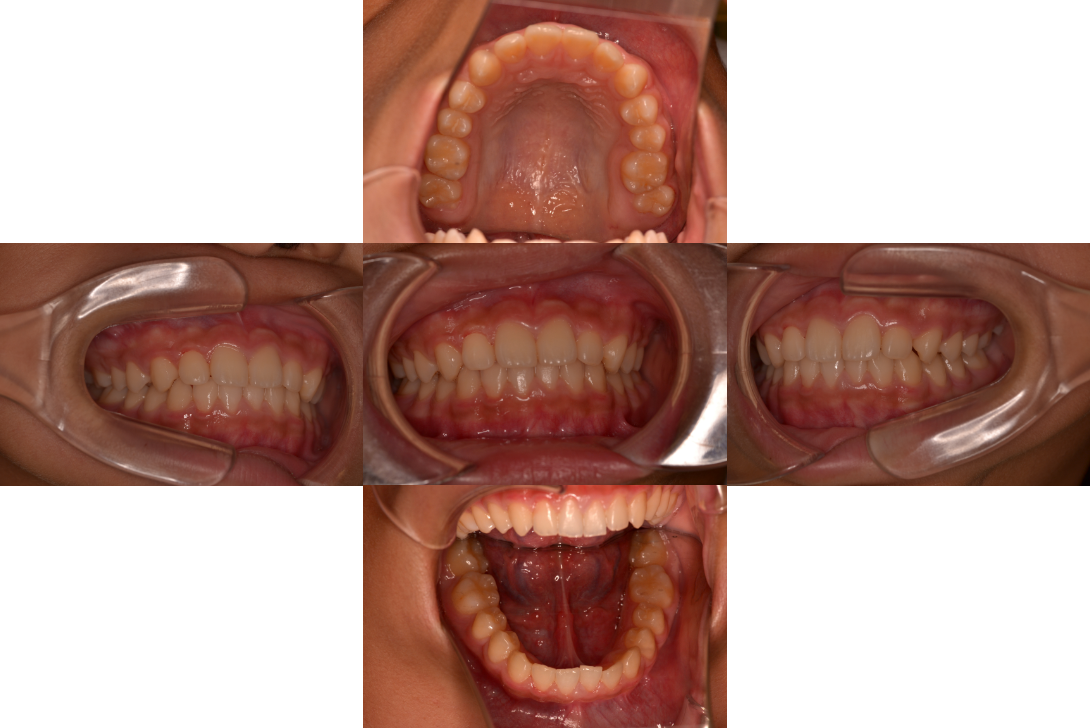

受け口(反対咬合・下顎前突)の症例

受け口(反対咬合・下顎前突)をリンガルアーチ、セクショナルDBSで改善した症例

10歳男性

前歯のかみ合わせ

リンガルアーチ、セクショナルDBS

歯根吸収、歯肉退縮

3年5か月